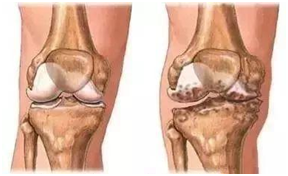

但是已经得了骨关节炎,确实需要保暖,除了及时穿上秋裤,最好尽量避免潮湿、寒冷的居住环境。膝关节两端骨表面有一层关节软骨,在人们走路、运动的过程中可以起到润滑、缓冲、减震的作用,进而对膝关节形成保护,而这层软骨一旦遭到破坏,膝关节两端就会出现“骨头磨骨头”的情况,进而引发无菌性炎症,出现疼痛、肿胀、灵活性下降、关节不稳等症状,严重时会影像走路。